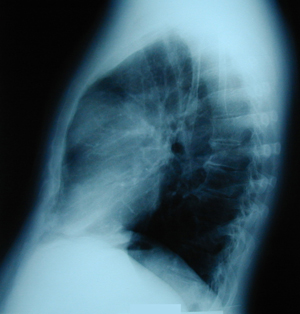

Εικόνα 2

Πλάγια ακτινογραφία θώρακος, στην οποία διακρίνεται μάζα στον οπισθοστερνικό χώρο στο ανώτερο πρόσθιο μεσοθωράκιο.